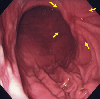

A case of type 3 advanced gastric cancer which morphologically showed an early gastric cancer-like appearance with scirrhous infiltration to the proper muscle layer.

Endoscopy